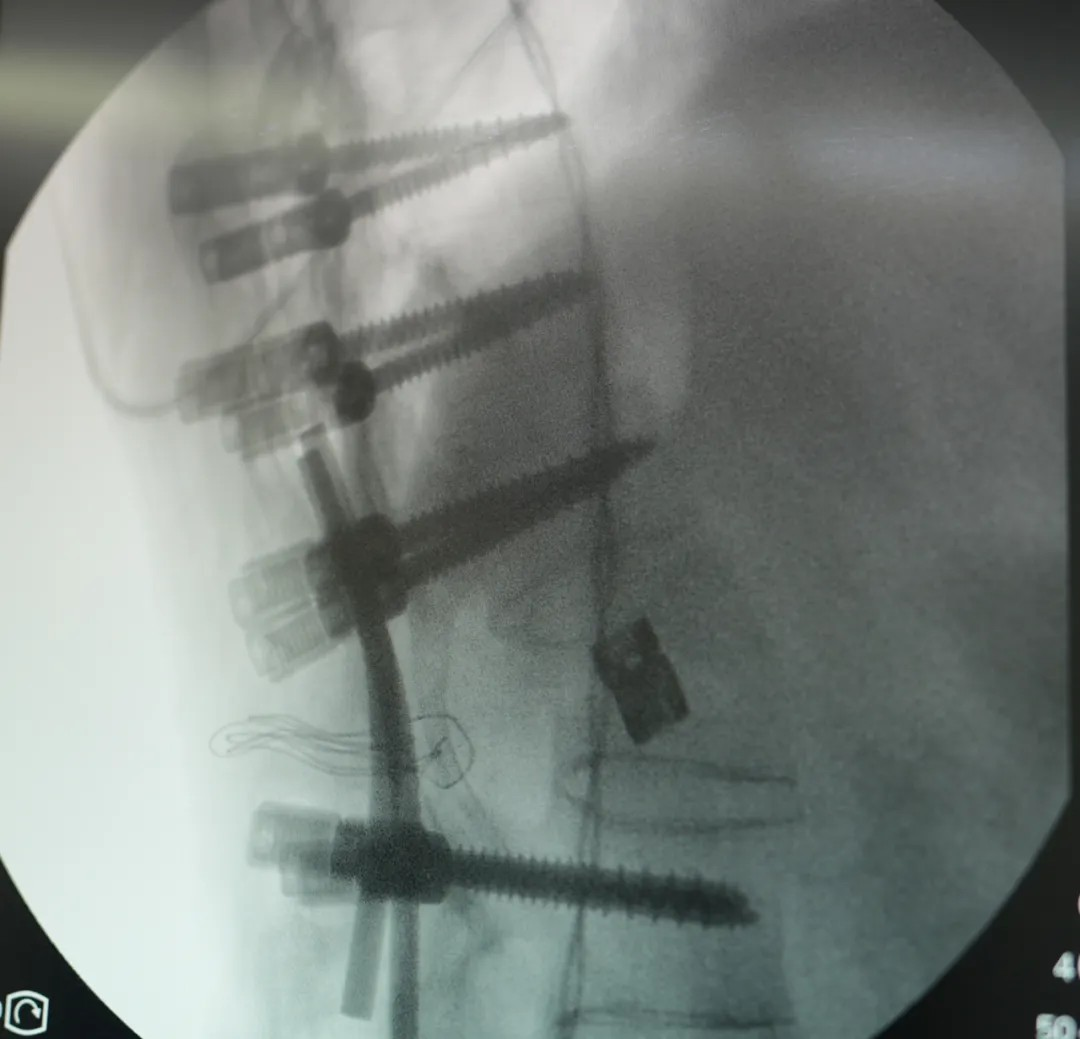

此次手术采用 PSO 截骨 —— 需要将患者病变椎体切除楔形骨块,再通过钉棒系统重新固定矫正。不同于常规脊柱手术,强直性脊柱炎患者因长期炎症导致脊柱 “骨化融合”,手术需面对解剖结构模糊、骨质疏松易骨折等多重风险。无论是截骨、置钉、矫形的哪个环节,都需要精准避开神经与血管,时刻关注脊髓神经的功能状态。

王宇主任团队使用超声骨刀、神经电生理监测设备,高效安全的完成了截骨、矫形,固定,达到了术前设计的预期。

在王宇主任团队与宜和骨科团队的配合下,手术从切开、截骨到内固定到缝合,全程时长4.5小时,比预期更顺利。患者术后三天即可开始康复训练、下地,1周左右拔掉引流管,10~14天即可出院。他的心肺功能会极大改善、脏器压迫被缓解,外形上也会恢复正常外形,很多人看不出来“做过手术”。